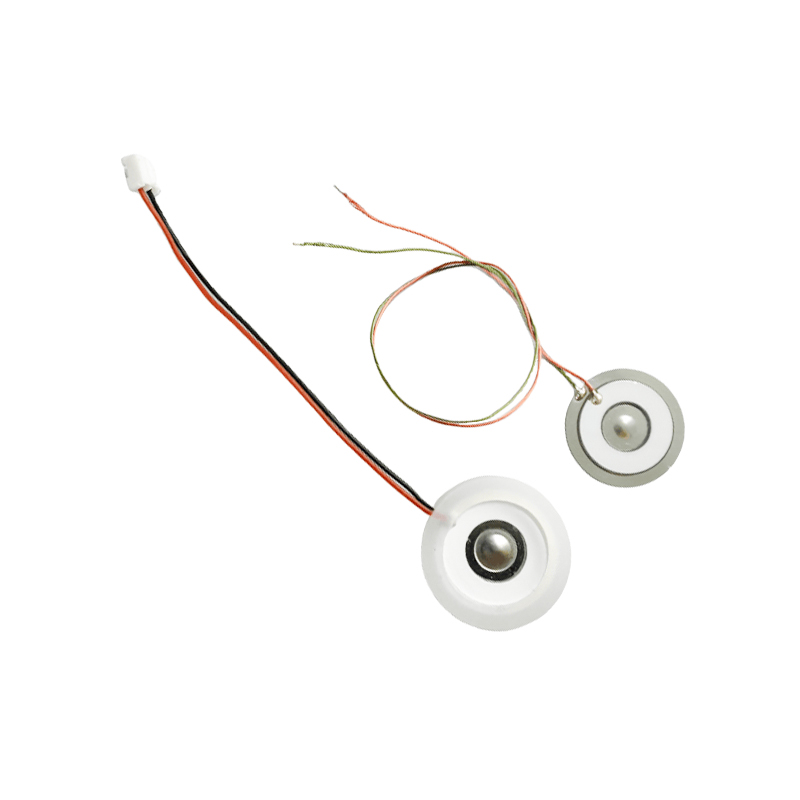

Les comprimés de nébuliseur à mailles médicales sont des composants de précision utilisés dans les dispositifs médicaux pour convertir des médicaments ou des solutions en minuscules particules d'aérosol pour le traitement de divers troubles respiratoires tels que l'asthme et la maladie pulmonaire obstructive chronique (MPOC), etc. par inhalation. La conception et le choix des matériaux de la feuille du nébuliseur sont essentiels pour garantir une administration efficace du médicament et le confort du patient. La feuille de diaphragme en acier inoxydable est percée de milliers de minuscules trous de maille de 2 à 3 µm dans la tôle d'acier grâce à une technologie de perçage laser dans un processus laser de précision, puis elle est étroitement liée à la feuille ronde en céramique piézoélectrique, qui convertit la fréquence de résonance de la feuille piézoélectrique en énergie de vibration haute fréquence via le signal de sortie de la carte de commande PCB, et décompose rapidement le médicament liquide en fines particules d'aérosol. Ces gouttelettes sont également appelées taille médiane des particules. Lorsque le pourcentage médian de la taille des particules D50 atteint > 60 % ou plus, les particules seront suffisamment petites pour pouvoir atteindre profondément les poumons jusqu'à la surface des alvéoles avec la respiration, améliorant ainsi l'efficacité d'absorption du médicament et l'effet thérapeutique. La feuille de nébuliseur à micro-mailles médicales a principalement plusieurs formes, une feuille de nébuliseur à micro-mailles en acier inoxydable, une feuille de nébuliseur médical en nickel palladium, une feuille de nébuliseur médical en polymère PI, etc. Tout ce qui précède se fait grâce à la conversion d'énergie de vibration piézoélectrique en céramique pour obtenir l'effet d'atomisation.

L'atomiseur à ultrasons est un appareil qui utilise le principe de vibration ultrasonique (conversion d'énergie) pour convertir le liquide en minuscules gouttelettes. Le principe de fonctionnement est que les propriétés piézoélectriques uniques de la céramique piézoélectrique de la décision, la pièce d'atomisation à la réception de l'excitation du signal de champ électrique correspondant, produira la fréquence d'oscillation correspondante, grâce au rôle de vibration à haute fréquence de la cavitation liquide rejetée de la surface de l'eau pour produire une sorte de particules de brouillard d'eau, atomisées avec un grand nombre d'ions négatifs et de petites particules de molécules, peuvent réaliser une augmentation de l'humidité ambiante, le rôle de l'air frais. La surface de l'atomiseur est recouverte d'émail vitreux à une température élevée de 800 degrés pour protéger les électrodes d'argent de la feuille piézoélectrique, augmenter la résistance aux acides et aux alcalis et la résistance à l'oxydation de l'atomiseur et augmenter la durée de vie de l'atomiseur. Largement utilisé dans les humidificateurs d'intérieur, les purificateurs d'air, le traitement par nébuliseur médical et les voitures de beauté, par exemple dans d'autres domaines, mais convient également aux entrepôts, aux usines, à l'humidification, à la désinfection, pour créer l'atmosphère des équipements d'humidification. Les comprimés de brumisation sont principalement utilisés dans l'humidification industrielle, la brumisation médicale, la brumisation d'aromathérapie, l'humidification environnementale, la brumisation de jardin et d'autres scènes.